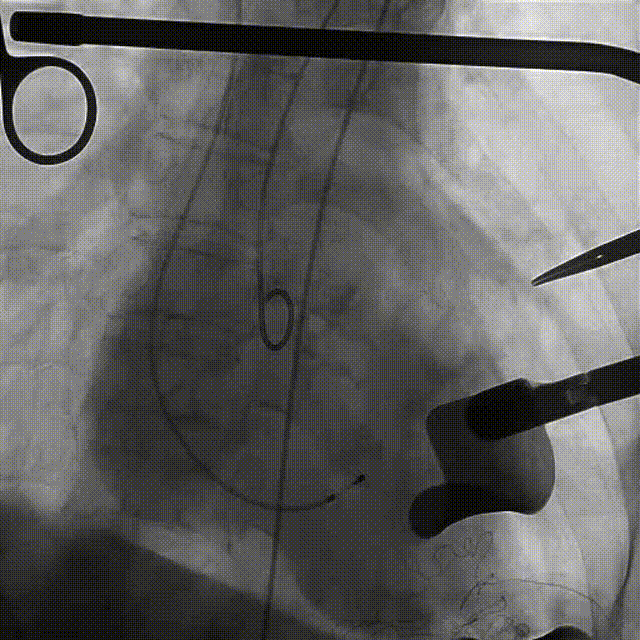

手术过程